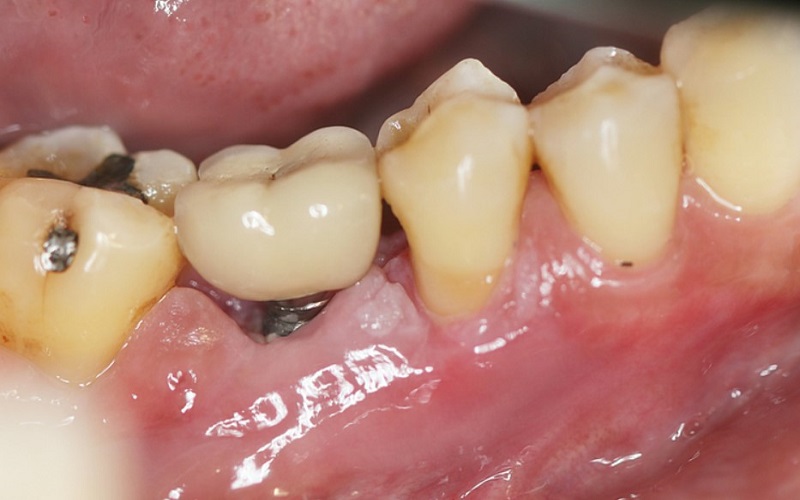

2. Sưng đỏ, chảy máu và có mùi hôi quanh trụ implant

Khi mô nướu quanh trụ bị nhiễm khuẩn, bạn có thể nhận thấy vùng nướu sưng đỏ, chảy máu khi chải răng và hơi thở có mùi. Đây là dấu hiệu sớm của viêm quanh implant (peri-implantitis) – tương tự như viêm nha chu ở răng thật.